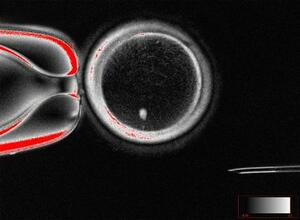

卵母細胞の核を除き、皮膚細胞の核を移植した細胞(中央)(米オレゴン大ミタリポフ研究室提供)

A 卵母細胞の核を取り除き、代わりに皮膚細胞の核を移植します。こうしてできた細胞82個を試験管内で受精させ、特定のタンパク質を与えたり、電気ショックなどの刺激を加えたりしたところ、移植された核...